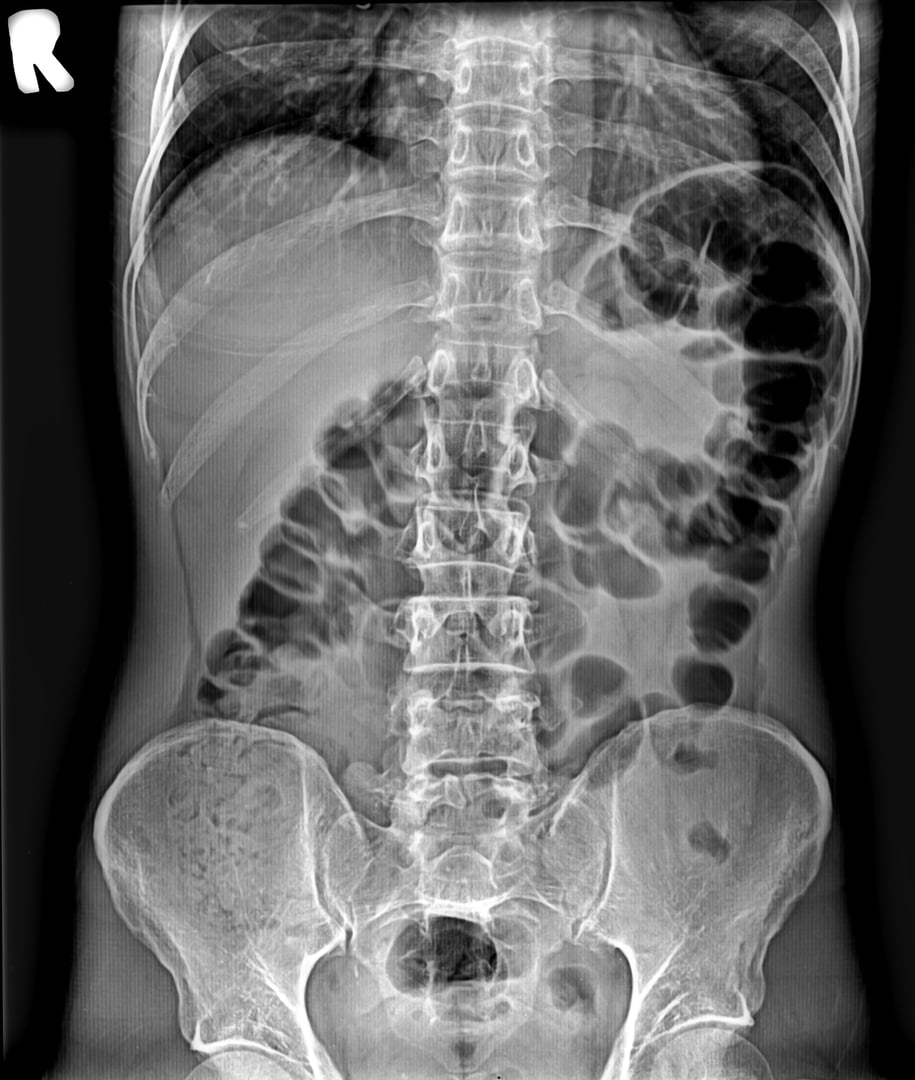

Enfermedad por Reflujo

Diagnóstico y tratamiento especializado del reflujo gastroesofágico en niños y bebés

Estreñimiento Crónico

Manejo integral del estreñimiento funcional y problemas de evacuación

Dolor Abdominal

Diagnóstico preciso y tratamiento del dolor abdominal recurrente o agudo